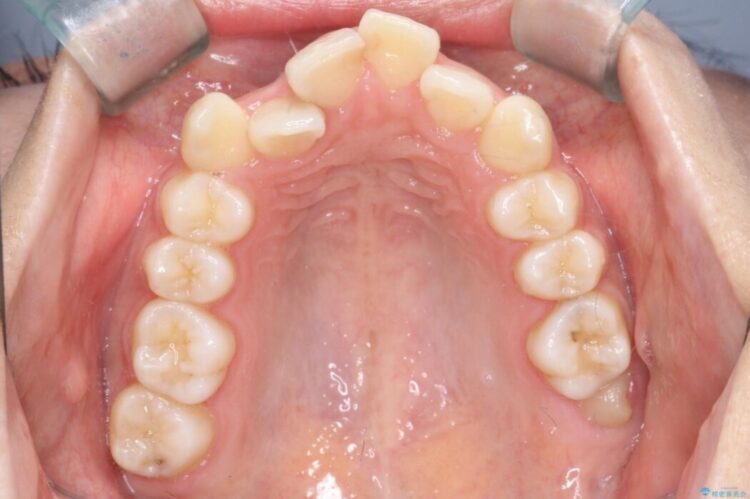

前歯のガタつきと、口元の突出感を改善したいと来院されました。

矯正検査の結果、歯を並べるスペースが不足しており、そのまま並べてしまうとさらに突出感が目立つ恐れがありました。

そのため上下左右4番を抜歯し、ガタつきを改善しながら前歯をしっかりと後方へ下げ、口元のボリュームを抑えていく計画を立案しました。

複雑に重なり合っていた前歯を、抜歯で作ったスペースを活用して丁寧に整列。単に並べるだけでなく、角度を1ミリ単位で調整しながら後ろへ下げることで、口元の突出感をスッキリ解消しました。